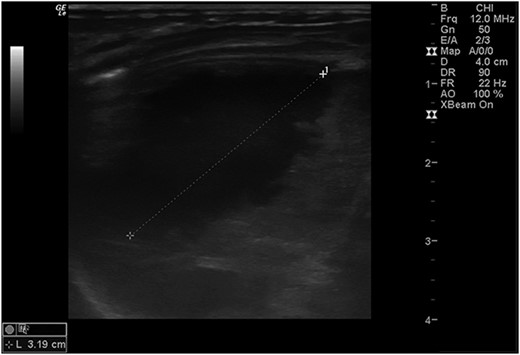

Postoperatively, a chest X-ray revealed a small left-sided pneumothorax that resolved in a few days (Fig. 2). Three days after the surgery, the fentanyl infusion was stopped, and the patient was extubated to a high-flow nasal cannula for 5 days. On the same day, the patient was noted to have a greenish-yellow aspirate. The patient was febrile the day after, a septic screen was done, and the patient was treated with ceftriaxone and vancomycin for 2 weeks. Furthermore, the surgical site was noted to have purulent discharge, for which fusidic acid was locally applied for 2 weeks. Abdominal ultrasound conducted a week after surgery showed an oval collection of fluid with intrinsic echoes, possibly a splenic hematoma, in the left upper quadrant, which was self-limited after 2 months of follow-up (Fig. 3). Before discharge, the patient’s parents were advised on a nursing plan, oral sucrose for analgesia and ranitidine.

Abdominal ultrasound conducted 1 week post-operatively showed a possible splenic hematoma, which was self-limiting.